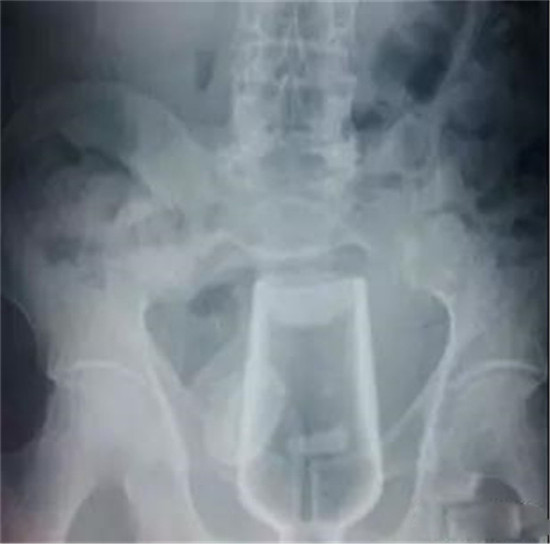

杯子。

这个还是比较常见的,认得出来吗?

男性病人,也是个杯子。

这个也是一个玻璃杯。